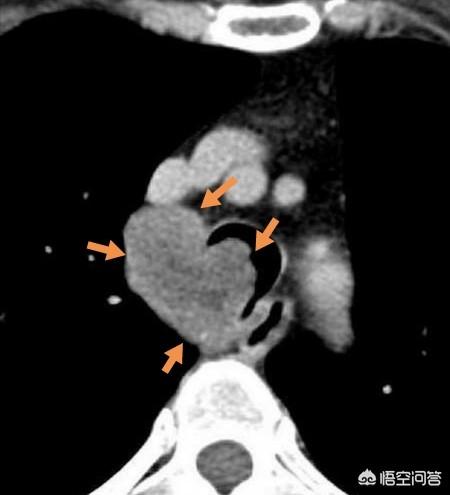

Chez des patients comme celui-ci, une tumeur musculaire lisse bénigne s'est développée sur la trachée, provoquant une sténose de la trachée et une dyspnée, et ce type de patient doit être opéré pour retirer la tumeur.

Il s'agissait d'un pneumocytome sclérosant, précédemment connu sous le nom d'hémangiome pulmonaire sclérosant, qui a été étudié comme étant bénin mais avec des tendances malignes, et qui a ensuite été enlevé chirurgicalement pour réduire également le risque.